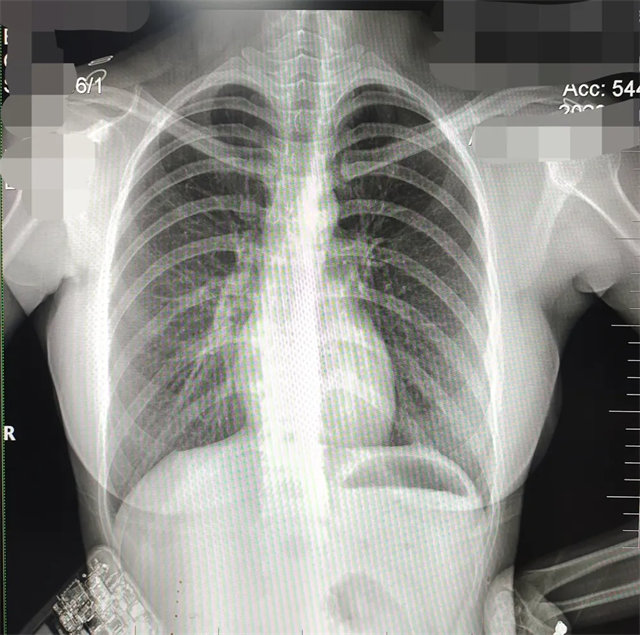

缺陷:兩肩胛骨未拉開肺野之外,吸氣不完全,且存在金屬飾品遮擋。

解決:去除金屬飾品及內(nèi)衣后重新按標準體位攝片即可。